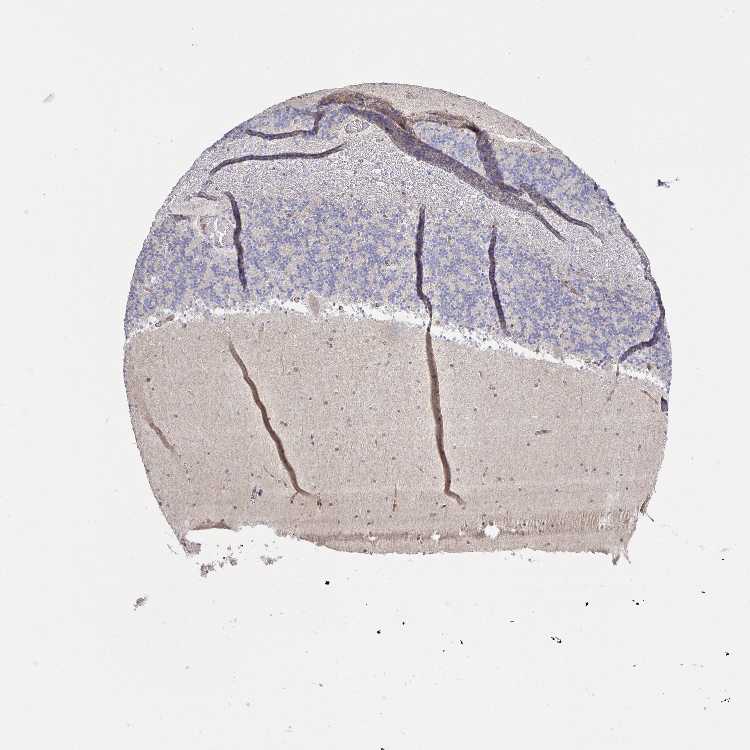

CEREBELLUM - Antibody stainingi

Antibody staining in the annotated cell types in the current human tissue is reported as not detected, low, medium, or high, based on conventional immunohistochemistry profiling in selected tissues. This score is based on the combination of the staining intensity and fraction of stained cells.

Each image is clickable and will lead to virtual microscopy that enables deeper exploration of all samples and also displays staining intensity scores, fraction scores and subcellular localization as well as patient and tissue information for each sample.

Antibody HPA040026Antibody HPA044090Antibody CAB008672

Purkinje cells Not detectedMediumNot detected

Cells in granular layer Not detectedLowNot detected

Cells in molecular layer Not detectedNot detectedLow